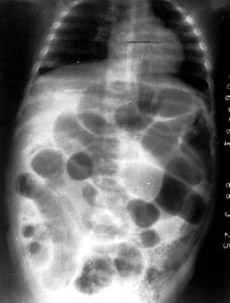

新生儿坏死性小肠结肠炎

疾病介绍:新生儿坏死性小肠结肠炎(NEC)是一种严重疾患,由多种因素引起,早产儿、小于胎龄儿发病者较多。肠道病变范围可局限或广泛,回肠最多累计,依次为升结…【详细】